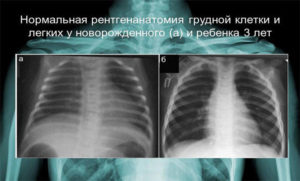

Это особенно важно при наличии подозрений на пневмонию, туберкулез или опухолевые процессы в легких. Боковая проекция позволяет визуализировать те участки органа, которые могут быть скрыты за грудиной или реберными дугами. Обычно врачи стараются избегать назначения «двойного» рентгена грудной клетки детям, чтобы минимизировать воздействие излучения на развивающийся организм.